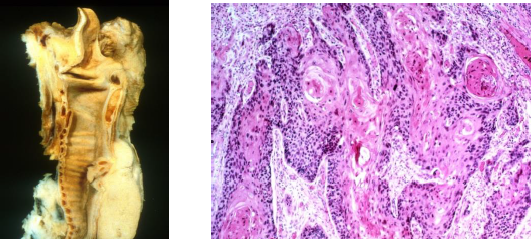

35

Pathology?

Peutz-Jegher syndrome melanotic mucosal and cutaneous pigmentation; hamartomatous polyps throughout GIT